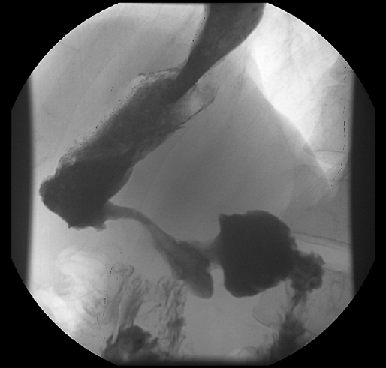

Во-первых, это длительное бессимптомное или малосимптомное течение, связанное с отсутствием острой манифестации различных осложнений (дисфагия, стеноз выходного отдела, перфорация) и проявляющееся различными формами диспепсии (которые в старых учебниках часто рассматривалось как ;синдром малых признаков).

Во-вторых, своеобразие рентгено-эндоскопических данных — диффузное изменение стенки желудка с развитием ригидности, циркулярного сужения (желудок изменен по типу кожаного сосуда) (рис. 1), утолщения стенок и плохого расправления складок на фоне инсуфляции воздуха. Своеобразие морфологической картины — гнездное включение опухолевых клеток в виде очагов в слизистую оболочку желудка с диффузной инфильтрацией слоев на фоне выраженной стромальной реакции с развитием интерстициального фиброза. Отличны подходы к тактике хирургического и комбинированного лечения. Однако главным отличием данной формы рака желудка является крайне неблагоприятный прогноз. Абсолютное большинство пациентов поступают на лечение в распространенных стадиях заболевания. Истинно радикальные вмешательства удается выполнить крайне редко, что отражается на отдаленных результатах — 5 лет наблюдения переживает не более 5% пациентов. Основным видом прогрессирования после радикального лечения является интраперитонеальный рецидив в виде канцероматоза брюшины.

Рисунок 1. Тотальный рак желудка